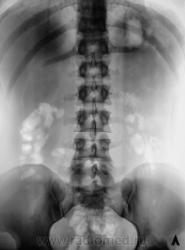

Пациент направлен на внутривенную урографию

Пациент направлен на внутривенную урографию.

Находится в хирургическом отделении. В отделение направлен из военкомата. Произведено стандартное исследование.

Пациент был прооперирован в 2009 году по поводу стриктуры в области лоханочно-мочеточникового сегмента справа.

Да, правый мочеточник проходим, это доказали томограммы.

Мне показалось, что имеет место быть перегиб самой лоханки.

В принципе, мы "режем" все, и в прямой, и в боковой проекциях. В данном случае показалось, именно, за счет перегиба лоханки, что имеется крупный конкремент в лоханке, и я ожидал получить, что-то в виде "дефекта наполнения". История, как и в большинстве случаев, чистая. Потом заставил пациента принести копию выписки из областной больницы. Выписка конечно "не блещет", но удалось выудить, что пациент был оперирован по поводу гидронефроза, который был обусловлен стриктурой.